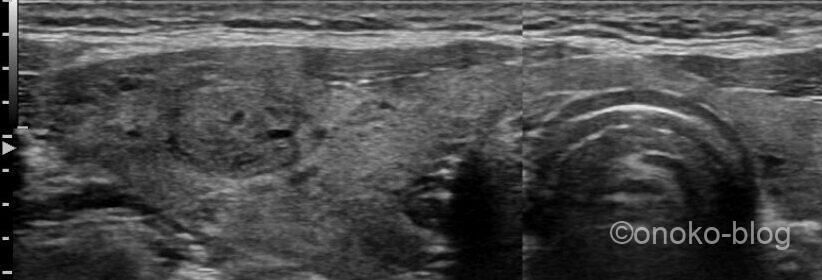

後日頸部も痛むということで、超音波検査がオーダーされた時の画像です。

一部辺縁低エコー帯を伴う結節を右葉に認めます。

内部は無エコーや点状高エコーも確認できました。

内部に血流信号も確認できます。

内部無エコーは腺腫様結節にみられるような spongiform pattern ではなさそう…

甲状腺超音波診断ガイドブックに則ると、良性と考えられるのか…でも

うーんなんとなく境界がはっきりしない…撮り方のせいかもしれないけれど、

明らか典型像には見えないのよね…と思い、その旨をレポートに記載。

結果は髄様癌でした。